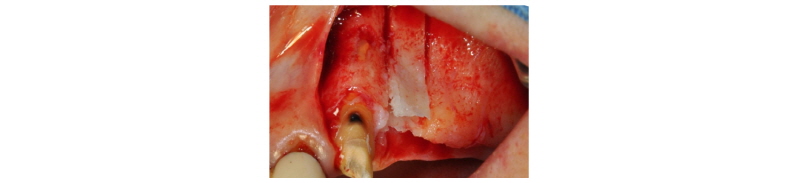

57세의 여성 환자로 기존 브릿지 보철 수복물(#24-27)의 상악 좌측 제 2대구치의 심한 우식으로 인해 내원하여 해당 치아를 발거하였다(Fig. 1). 상악 좌측 제 1 소구치는 근관치료를 시행한 후 보철 수복하기로 하였고 기존 pontic 부위였던 좌측 제 2 소구치와 발거된 제 2 대구치 부위에 #25i, #27i 2개의 임플란트 식립을 통한 브릿지 보철 수복물을 계획하였다(Fig. 2). 기존 pontic으로 유지되었던 좌측 제 2 소구치 부위는 치조제의 심한 수평적 치조골 흡수를 구강 내 임상검사를 통해 확인할 수 있었다. 전층 판막 형성후 상악 좌측 제 2 소구치 부위의 치조정 폭경은 약 2 mm 정도로 측정되었다(Fig. 3, 4). 치조골의 구개측에 약 1 mm의 치조골이 남도록 high speed carbide round bur를 이용하여 치조정에 horizontal intraosseous groove를 형성하였고 협측골의 근심, 원심측에 2개의 vertical intraosseous groove를 형성하였다(Fig. 5). Chisel과 ridge spreader drill (RS kit, Dentium, Korea)을 이용하여 점차적으로 협측 골판을 구개측으로부터 분리시켰다(Fig. 6). Osteotome을 이용, 식립 깊이까지 적용하여 임플란트 식립 부위를 형성하였고 Ø4.3 × 10 mm (Implantium, Dentium, Korea) 임플란트를 식립하였다(Fig. 7). 발치 후 치유된 상악 좌측 제 2 대구치 부위는 상악동 거상술(수직 접근법)을 시행, 골이식을 한 후 4.8 × 10 mm (Implantium, Dentium, Korea)를 식립하였다(Fig. 8). 이후 이종골 이식재(Bio-Oss®, Geistlich, Switzerland)를 식립된 임플란트와 협,구개 측 치조골판 사이의 gap과 협측골판 상방에 적용하고 흡수성 교원질 차폐막(Bio-Gide®, Geistlich, Switzerland)로 피개한 다음 감장절개를 통해 장력없이 봉합하였다(Fig. 9-11). 이후 구강 내 검사 및 방사선 검사를 통해 수술부위 치유상태를 확인하였고 특이한 임상적 소견없이 정상적으로 잘 치유되었다(Fig. 12). 약 3개월 10일 정도의 치유기간 후 이차수술을 시행하였다(Fig. 13). 판막 거상 후 치조제 분할술을 시행하였던 상악 좌측 제 2 소구치 부위에 잘 형성된 신생 골양조직이 관찰되었다(Fig. 14). 상악 좌측 제 2 소구치 부위와 상악 좌측 제 2 구치 부위에 치유지대주를 장착하였고 상악 좌측 제 1 대구치 부위에 추가적으로 임플란트를 1회법으로 식립하였다(Fig. 15). 이차수술 이후 정상적으로 치유가 진행되어 약 2개월 후 최종 보철물 수복을 하였다(Fig. 16, 17). 약 1년 정도의 follow-up시 구강 내 검사와 방사선 검사를 통해서 임플란트 주위 연조직과 변연골이 잘 유지되고 있음을 확인하였다(Fig. 18).

|

Fig. 11. Flap was closed with tension-free sutures. |